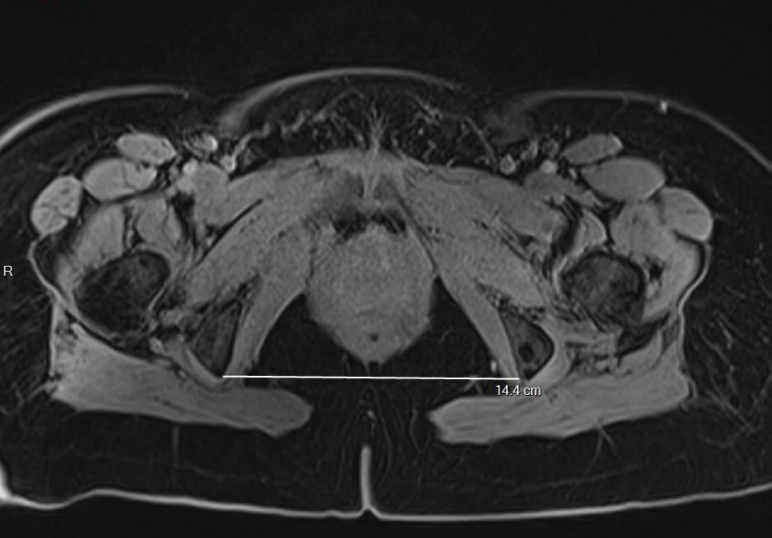

Sur les coupes transverses :

- Sur la coupe passant par les fovea des têtes fémorales, la distance interépineuse, la distance la plus étroite entre les épines sciatiques ;